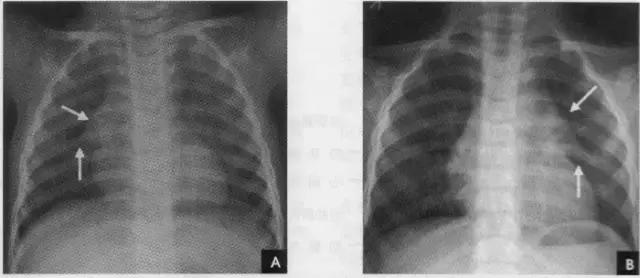

2、横裂又称水平裂,约70%的人正、撼位胸片均可显影。在正位片上表现为右中肺野横行细线状阴影,从第6肋腋部水平自外向内延伸.并止于肺门外lcm处。可向上或向下倾斜10:左右或略成曲线;在侧位片上,横裂起白斜裂中部,向前呈水平方向走行达前胸壁。其位置的改变可作为判断肺体积变化的标志(如上图)。